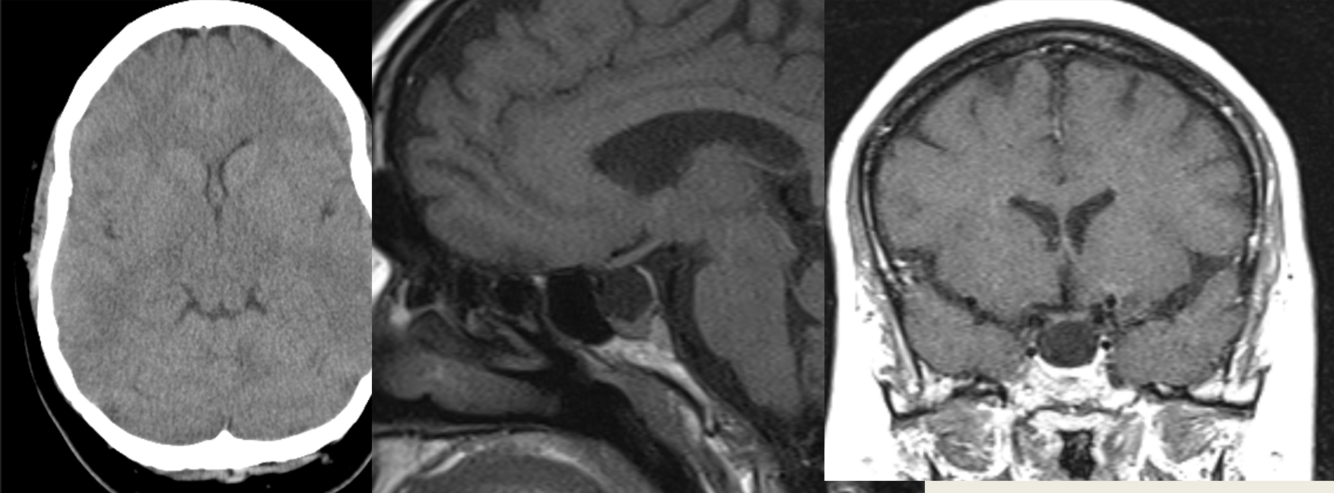

45 y/o M with bitemporal hemianopsia.

Meningioma arising from dorsum sella